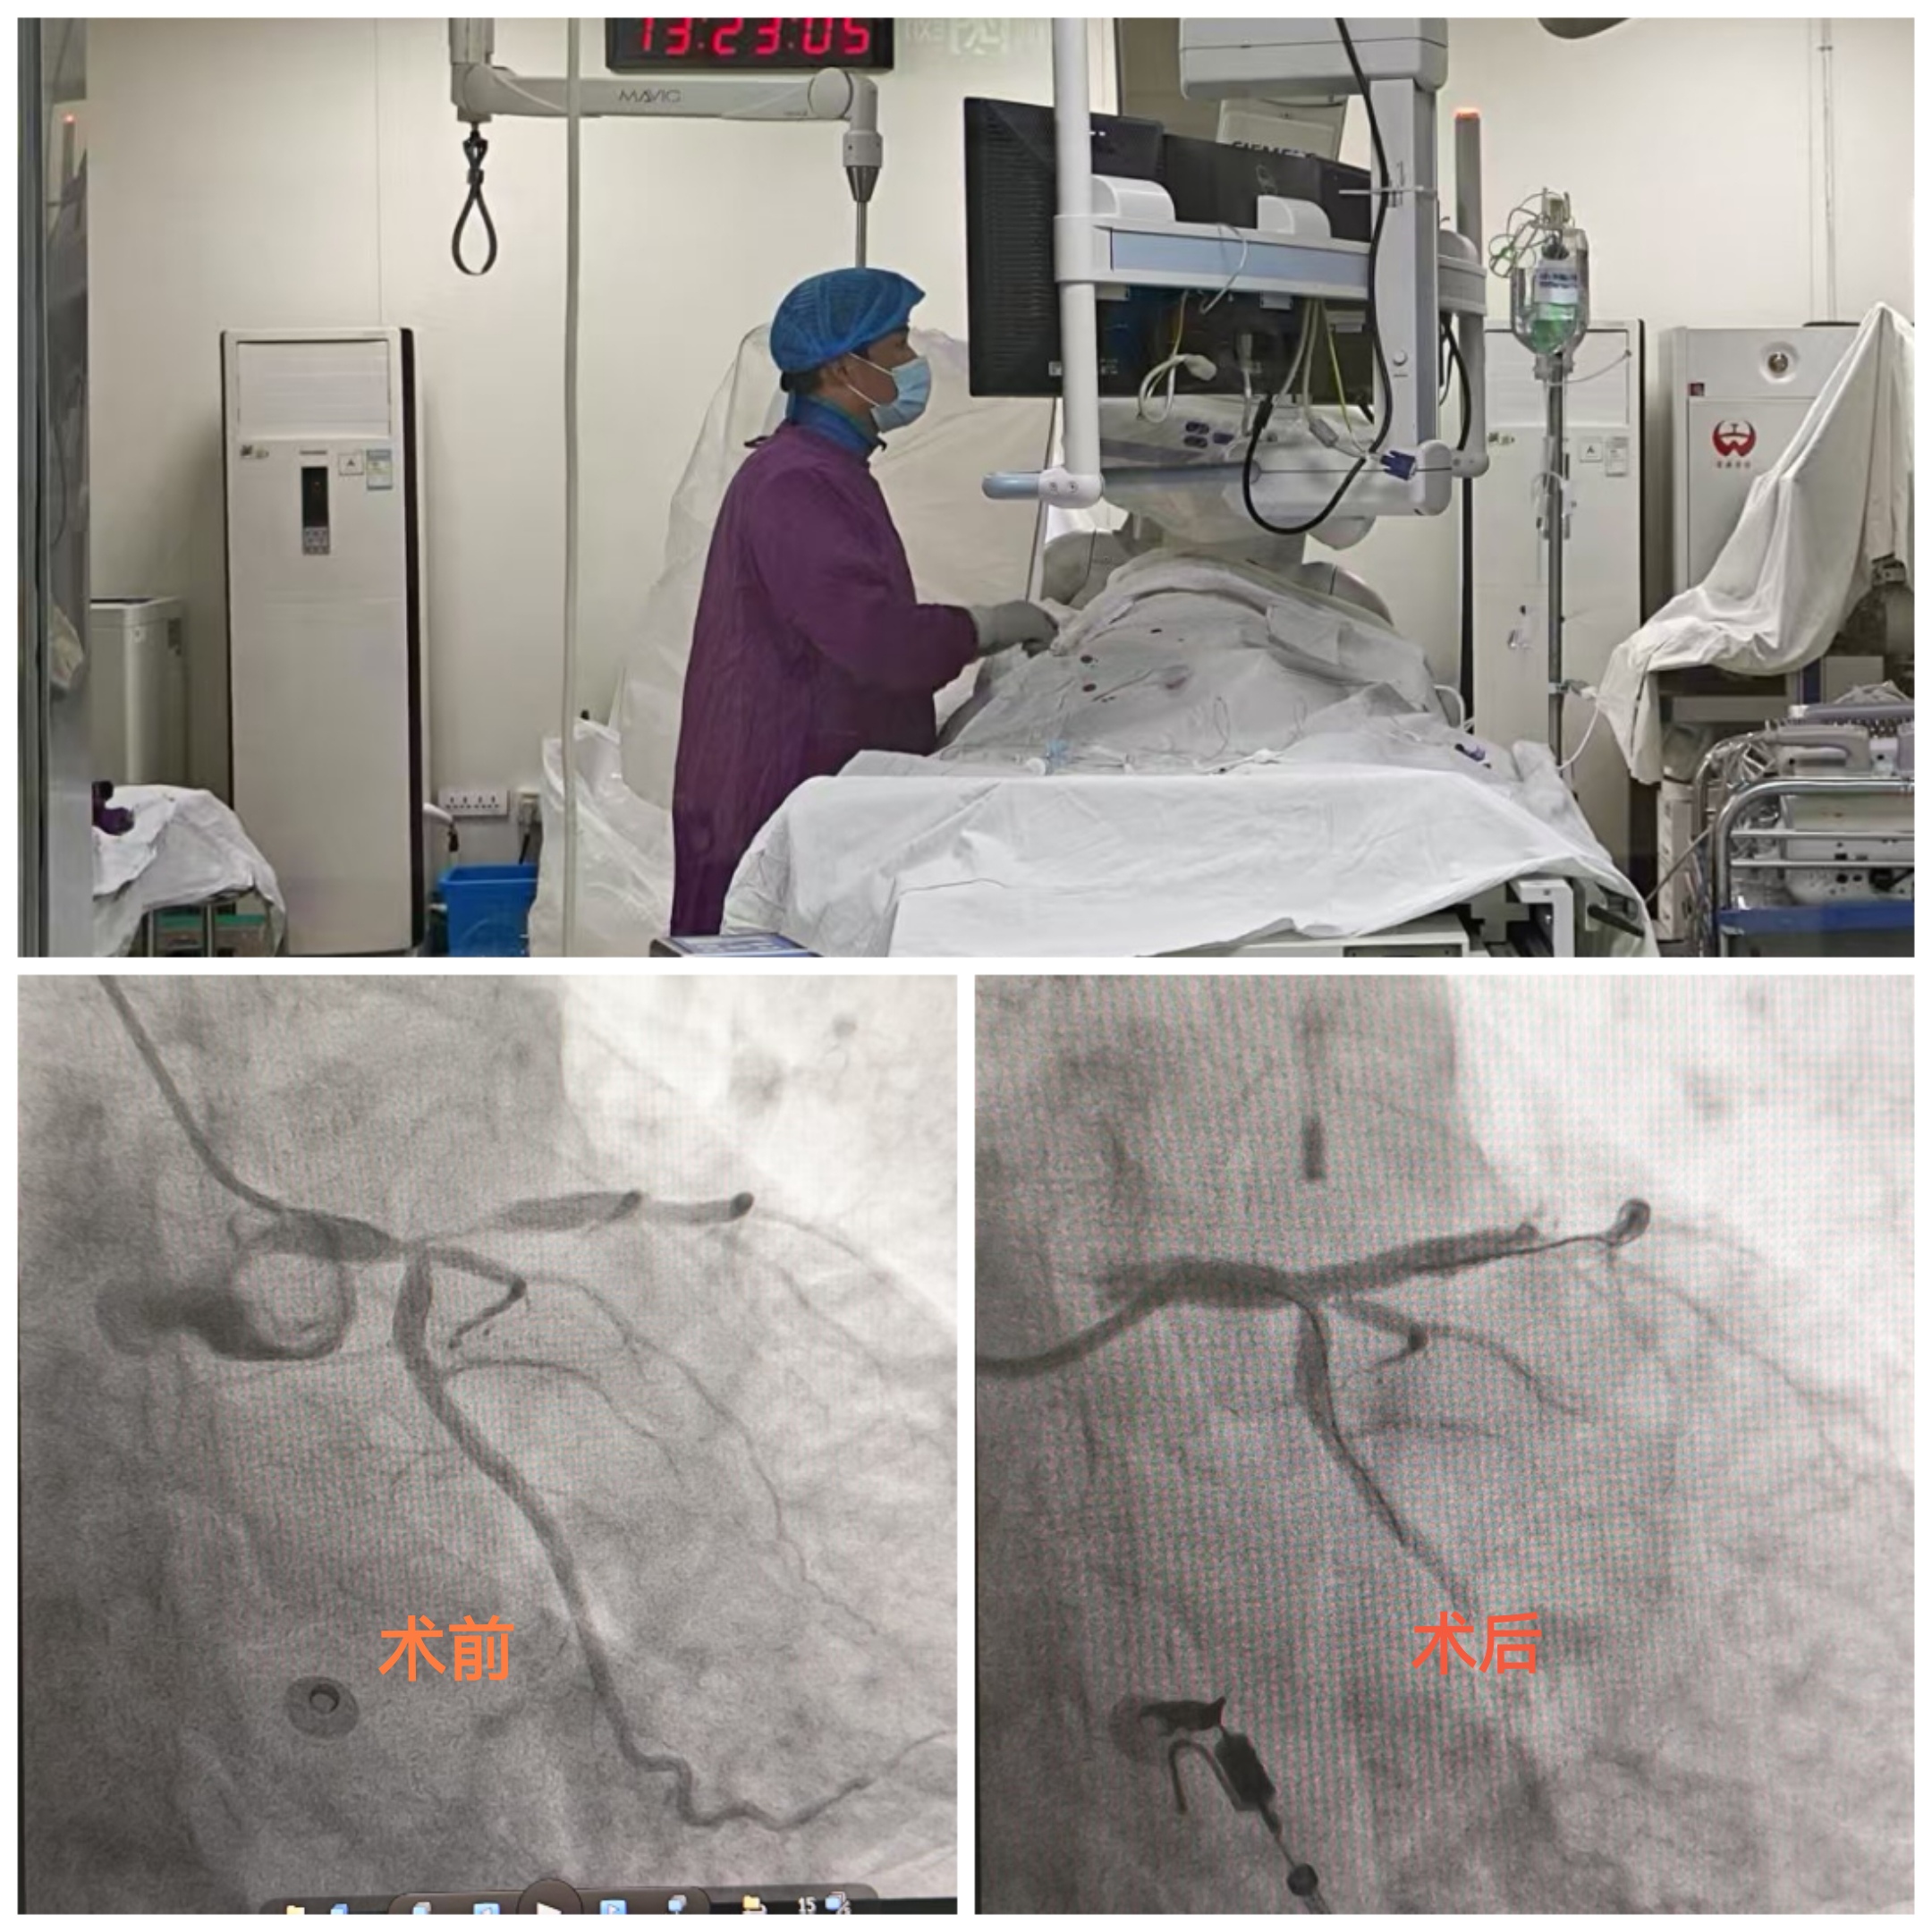

一位老人在健康管理中心进行健康体检,行心电图检查时提示V1-V5异常Q波伴ST段抬高,T波改变。经验丰富的心功能科医生敏锐捕捉到异常波形,凭借专业的医学判断,高度怀疑患者为急性心肌梗死。心功能科医生立即按危急值流程通知健康管理中心医护人员。健康管理中心迅速开通绿色通道,安排患者立即前往胸痛门诊就诊。胸痛门诊医护团队第一时间启动胸痛中心患者救治流程,完善相关检查。经确诊,患者高度怀疑为急性心肌梗死,情况十分危急。心血管内科一病区医生立即启动程序为患者进行救治,成功为其植入心脏支架,开通堵塞血管,患者转危为安。此次救治过程,从体检时发现异常到手术成功,各环节无缝衔接、高效运转,充分展现了医院在急危重症救治方面的卓越能力。